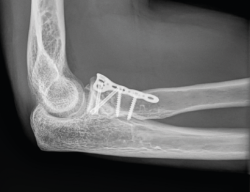

- Reducción abierta y fijación interna (RAFI): el objetivo es obtener una fijación anatómica y estable. Usaremos tornillos canulados de minifragmentos a compresión, sin cabeza, que dejaremos a nivel subcondral (Figura 3). Si existe afectación del cuello, lo ideal es sintetizar primero los fragmentos de la cabeza y añadir después algún tornillo hacia la diáfisis o una placa de bajo perfil (Figura 4)(13).

Figura 3. Ejemplo de fractura de Mason II tratada con 2 tornillos de minifragmentos canulados. A: imagen sagital en tomografía axial computarizada (TAC); B y C: radiografía anteroposterior y lateral de control a los 6 meses.